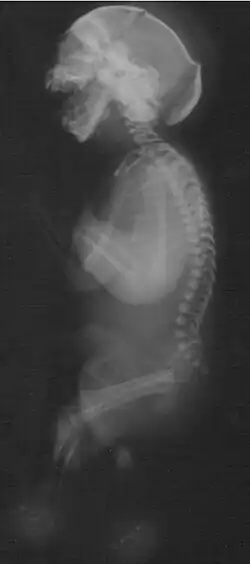

Das Neu-Laxová-Syndrom (auch: Neu-Syndrom, Neu-Povysilová-Syndrom; abgekürzt NLS; engl. Neu-Laxová syndrome) ist ein absolut letal verlaufendes angeborenes Fehlbildungssyndrom, gekennzeichnet durch ein behindertes Wachstum des Fötus und eine Reihe körperlicher Missbildungen.

Zum Krankheitsbild dieser seltenen Erkrankung gehört eine Vielzahl angeborener Fehlbildungen, darunter:

- Fehlbildungen des zentralen Nervensystems:

- Lissenzephalie

- Corpus-callosum-Agenesie

- Mikrogyrie

- Mikrozephalie

- Ödeme der Subkutis

- Ichthyose

- Muskelatrophie

- Fehlstellungen von Fingern und Zehen

- Arthrogryposis multiplex congenita

- Fehlbildungen der Nieren

- Herzfehler

- prominente Fersen

- Syndaktylie der Zehen

- Hypoplasie der äußeren Geschlechtsorgane

- Hypertelorismus

- fehlende Augenlider

- verkürzter Hals

Ätiologie